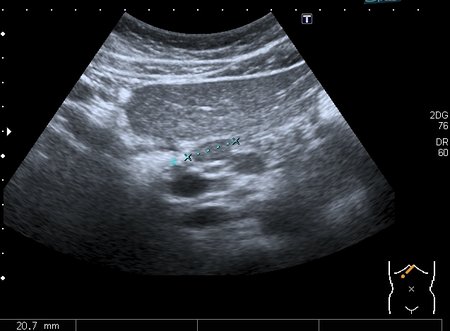

Девочка 13 лет, в течение 2-х недель температура до 38, СОЭ - 40 мм\ч, СРБ - 30.

На УЗИ: Учитывая клинику, лабораторные данные поставил гистиоцитарную инфильтрацию печени и селезёнки при генерализованной инфекции. Несколько раз встречался со схожими случаями, на фоне антибиотикотерапии изменения уходили. Но в данном случае девочка уже получала антибиотики в течение недели, на этом фоне не получено ни клинического , ни лабораторного улучшения, а на УЗИ очаги стали больше. Нужно ли расширять дифференциально -диагностический ряд? Ваши мнения

Имхо, по УЗ-семиотике - множественные небольшие абсцессы.

Мне нравится информация по данной патологии из видаровского "Клинического руководства по ультразвуковой диагностике в педатрии". Там данные изменения носят название очаговых поражений инфекционной этиологии (иерсиниоз, псевдотуберкулёз, токсокароз, хламидиоз и др.). Но инфекционисты, проведя ИФА с очень скудным набором диагностикумов и получив отрицательный результат, так же говорят, что это "не их".

В наше время тактика ведения абсцессов немного изменилась - крупные абсцессы (более 3 см в диаметре) дренируют, мелкие (менее 3 см) лечат антибиотиками.